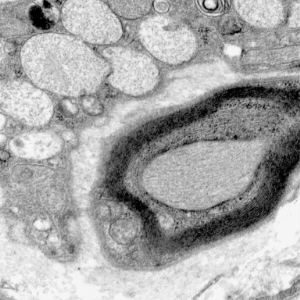

- ultrastructural findings useful in diagnosis

- lysosomal vacuoles with ill-defined contents

- may see glycogen granules

Lysosomal vacuoles in mucolipidosis (skin biopsy)